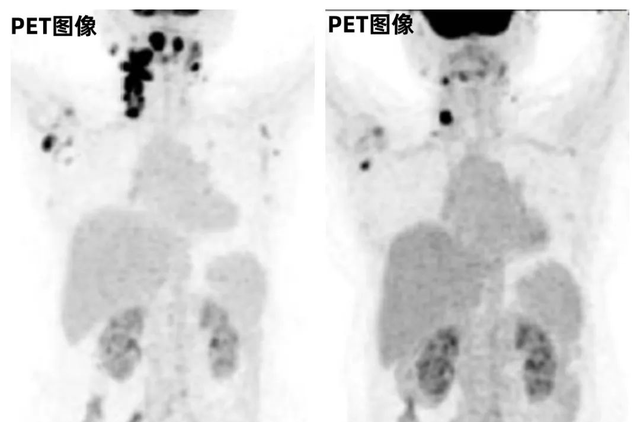

这位患者确诊为胰腺导管腺癌(PDAC)并已发生肝转移,影像检查显示胰腺肿瘤体积达6cm×2.5cm×3cm,肝脏最大转移灶直径3.5厘米。

由于肿瘤已无法手术切除,且患者拒绝传统化疗方案,医疗团队为其制定了CAR-NK细胞免疫治疗方案。令人振奋的是,治疗后患者的胰腺原发灶和肝脏转移灶均得到有效控制。